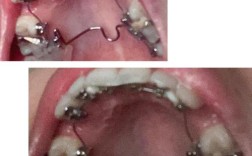

若需弯制滑动关闭曲(用于关闭拔牙间隙):

- 用梯形钳在弓丝标记点处(通常距尖牙托槽前2-3mm)弯制“Ω”形曲,曲的高度为4-5mm,宽度为2-3mm,避免曲过大刺激黏膜;

- 用持针器将关闭曲两侧的弓丝向龈端弯曲15°,使其与牙面贴合。

若需弯制牵引钩:用梯形钳在弓丝标记点处弯制“L”形或“T”形钩,钩的长度以不超出对侧牙面为宜,末端磨圆钝。